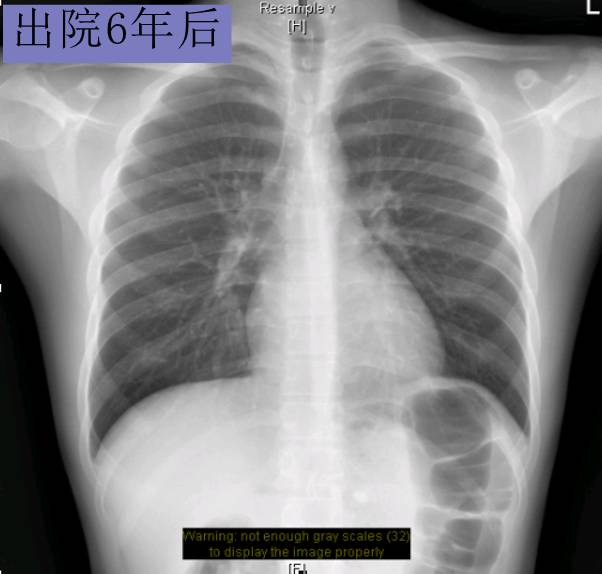

随访转归

► 7月后复查:心脏缩小,心功能好转

► 2年后病情平稳,复查超声心动图、NT-proBNP等大致正常。仅口服比索洛尔10mg qd+贝那普利5mg qd

► 3年后复查HOLTER:频发房早32925次,短阵房速。 患者心率控制在70-90bpm,超声心动图依然大致正常。未再出现胸闷,浮肿等症状。

► 6年内多次复查,UCG正常。无心衰症状。

► NT-proBNP 8787.94pg/ml(入院时)→540.1pg/ml(1年后)→ 378.4pg/ml(2年后),后多次复查均正常